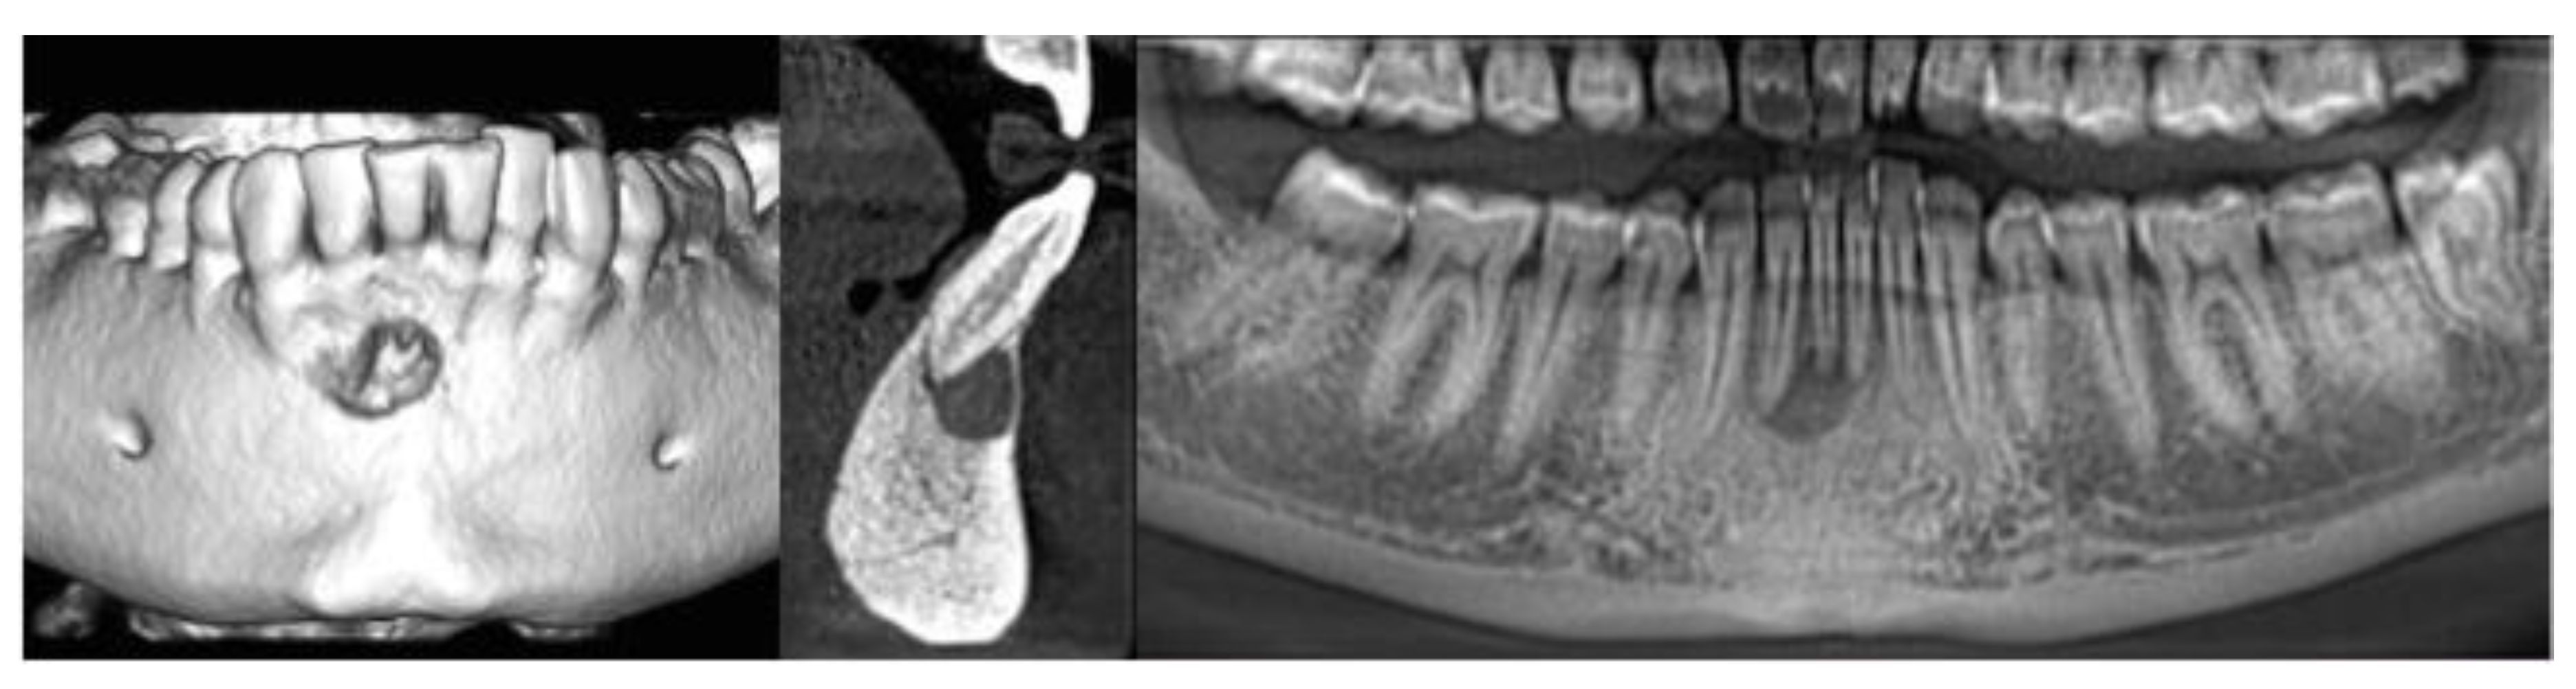

3D Assessment of Endodontic Lesions with a Low-Dose CBCT Protocol

2. Materials and Methods

3. Results